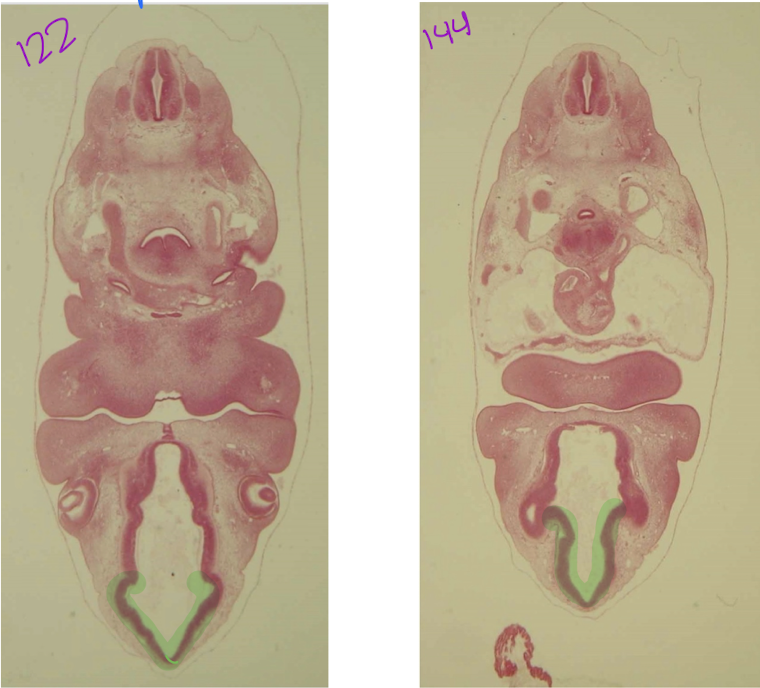

blue: dorsal root

green: dorsal root ganglion